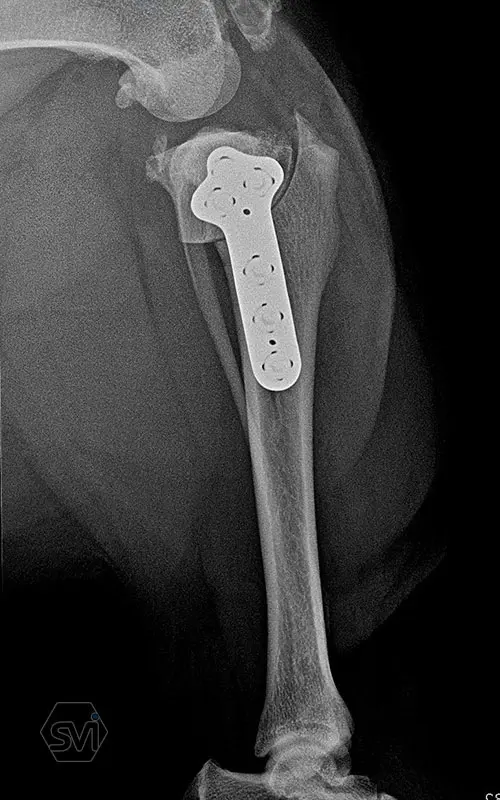

Introducing the precontured polyaxial locking TPLO family, now available in all sizes:

- Mini: 2.0mm (thinner and thicker version)

- Midi: 2.4mm

- Small: 2.7mm

- Standard: 3.5mm (both in short and extended versions)

- Giant: designed for 4.0mm screws.

It has a number of advantageous features that make it stand out from standard TPLO solutions:

- well designed that follows the anatomical position and ideal hole placement

- precontoured, its use shortens the surgical time, no greater physical force is required for bending

- locking system for greater stability

- polyaxial screw insertion, the direction of screw insertion can be freely selected in a 30-degree circle while maintaining angular stability! (this is very useful to avoid driving the screw into the joint, and the temporary fixing can also be avoided with a K-wire)